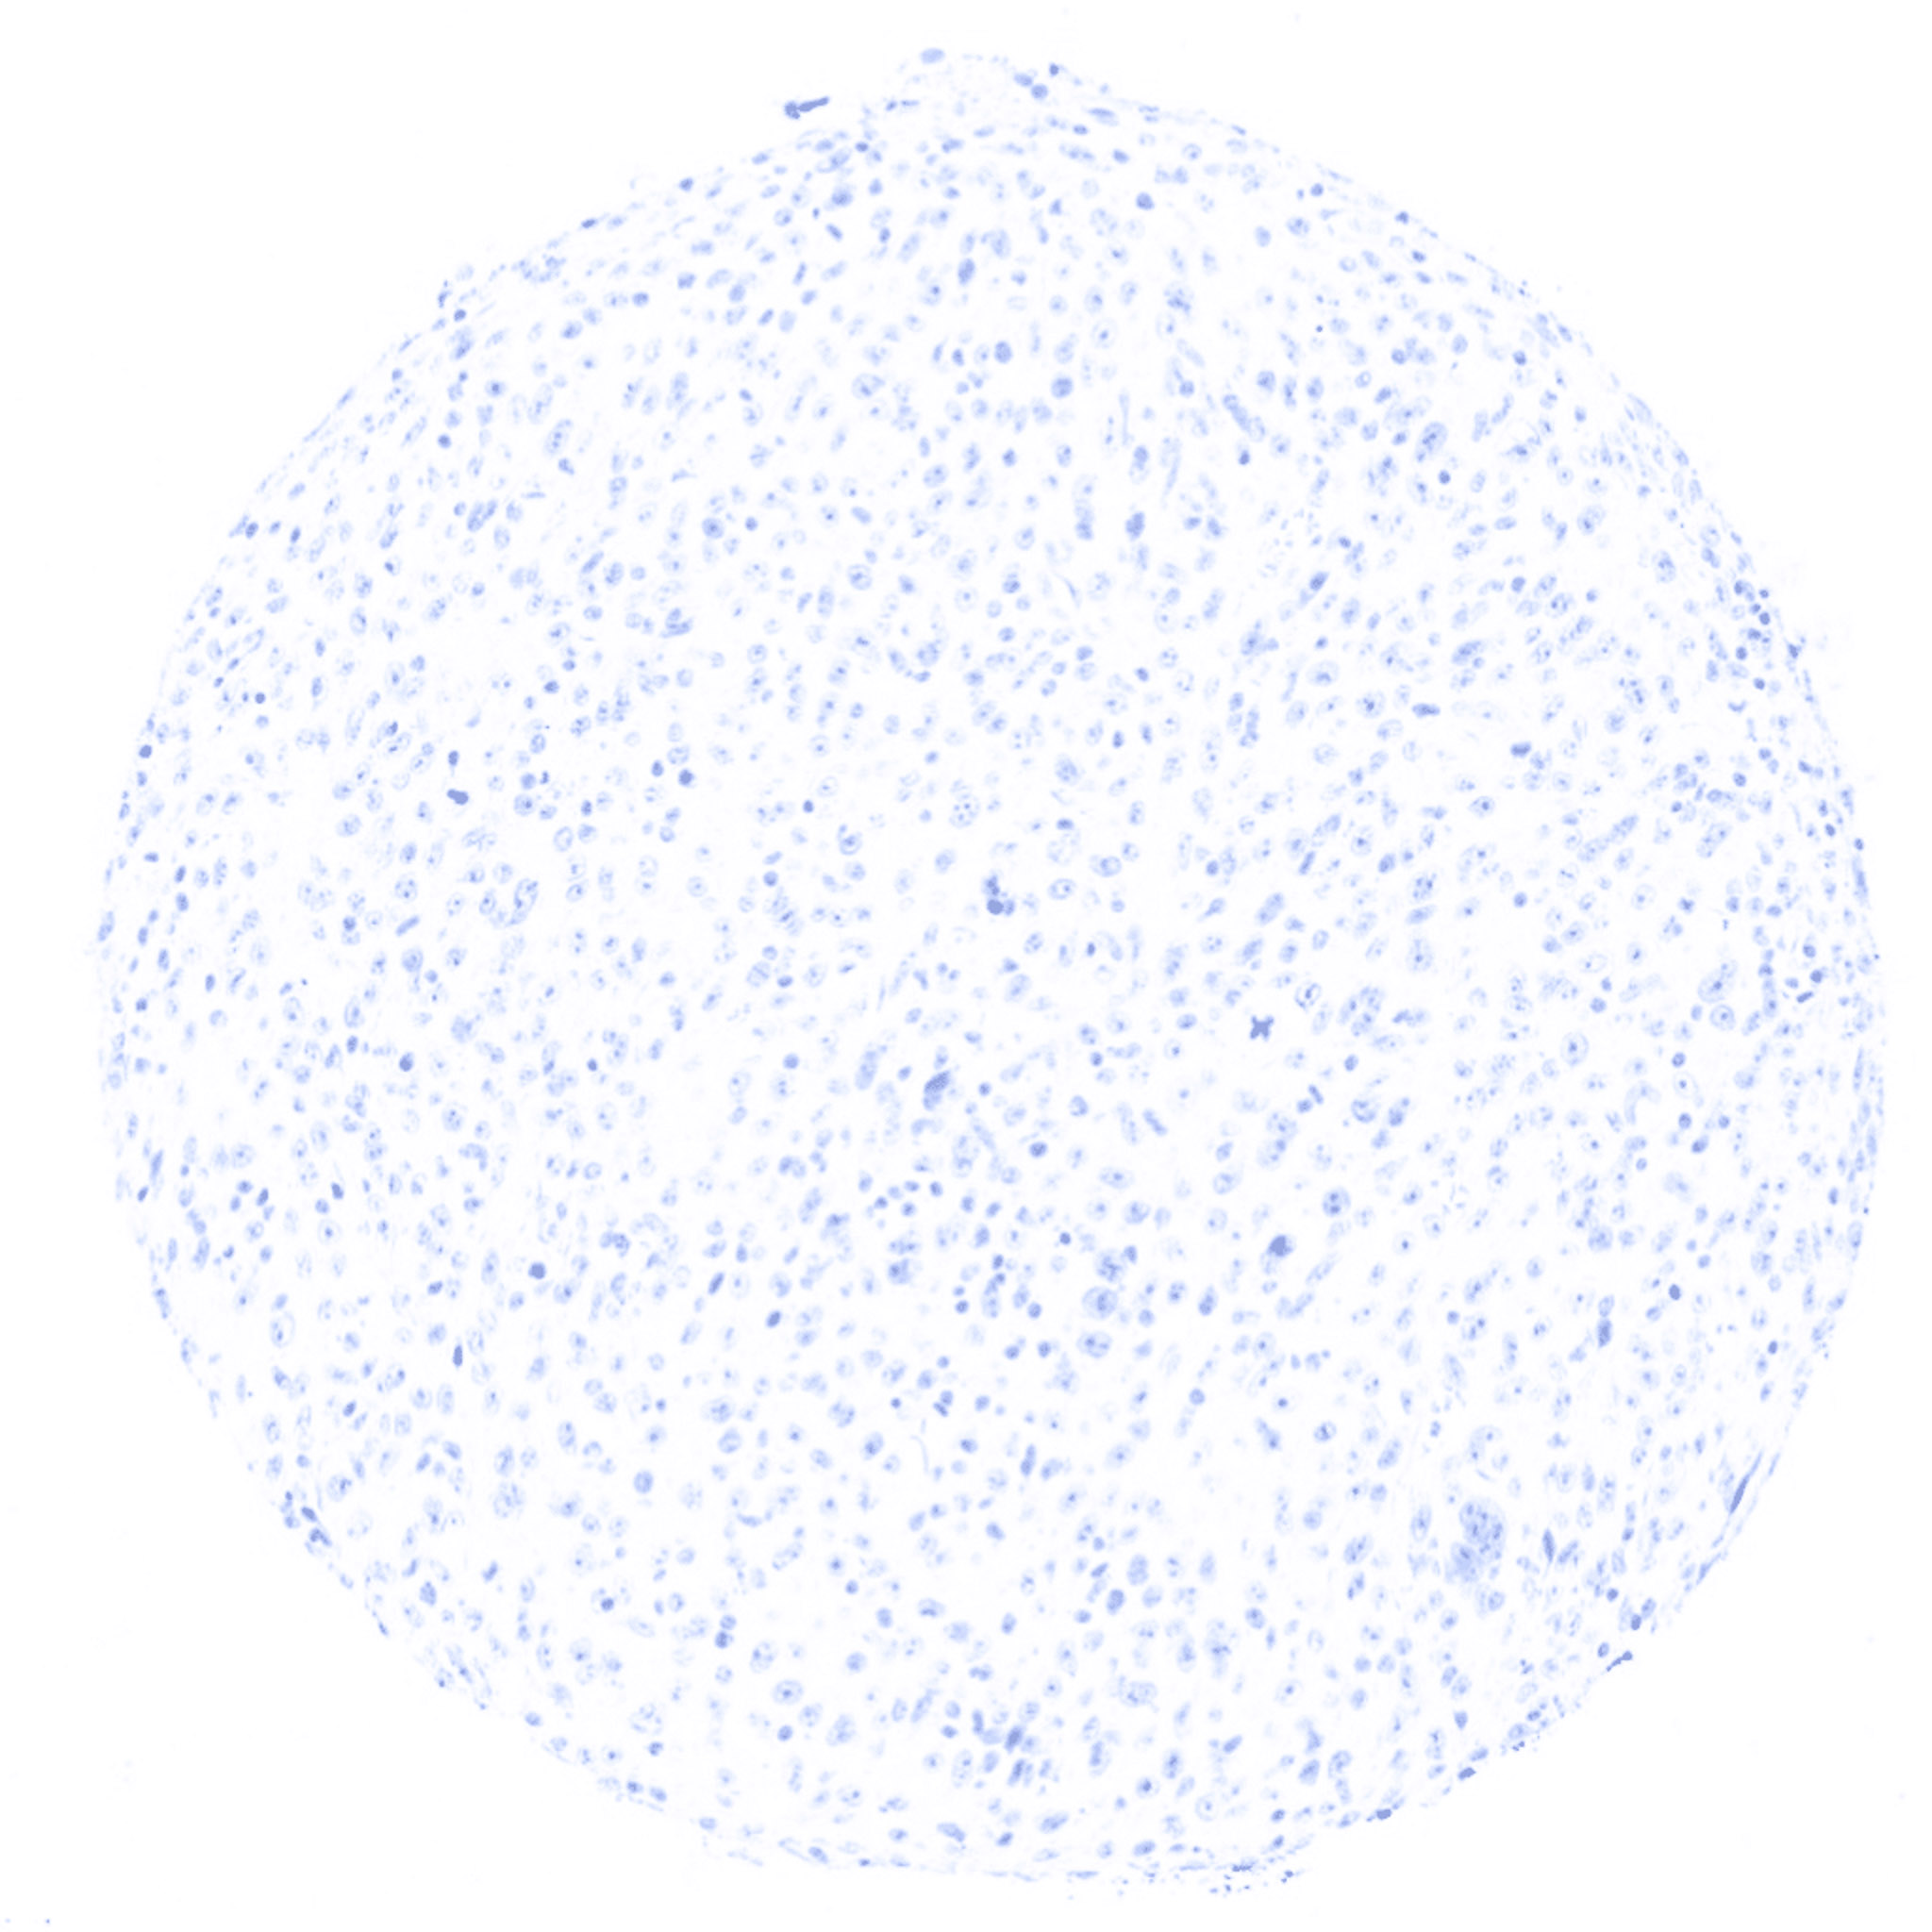

Thyroglobulin negative anaplastic thyroid cancer.